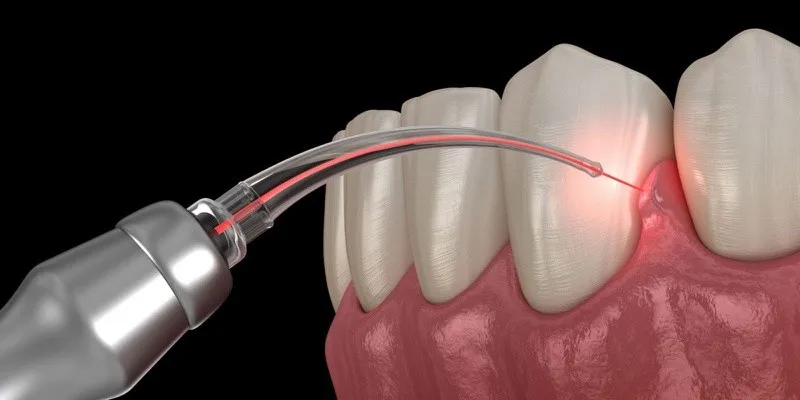

Cắt lợi bằng laser đang ngày càng phổ biến nhờ khả năng thẩm mỹ nướu nhanh chóng, giúp khắc phục cười hở lợi hoặc nướu thừa một